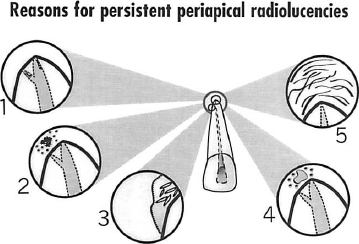

In a series of studies that have analysed the reasons for failure, four reasons for biological failure have been identified. These include persistent intraradicular microorganisms,9 extraradicular infection,10,11 extraradicular foreign material12 and true cysts especially those containing cholesterol crystals.13

Fig. 3.–Reasons for persisting periapical radiolucencies when endodontic treatment has been performed to a high standard include: 1, Intraradicular microorganisms in unfilled spaces in the canal; 2, Extraradicular infection; 3, True cyst with cholesterol crystals; 4, Extraradicular foreign material; and 5, Healing by fibrous scar tissue.

Recently, a fifth factor associated with persistent periapical radiolucencies has been identified.14 This study examined cases in which the endodontic treatment had been performed to a high standard, but on follow-up there was a persistent periapical radiolucency.14 When correlative light and electron microscopy was performed on the biopsies, two cases involved an intraradicular infection, one case was a cyst, and two cases revealed fibrous scar tissue healing following conventional treatment. This means that in rare cases a persistent radiolucency may be misinterpreted as a failure when the periapical lesions heals with fibrous scar tissue.

In summary, there are five reasons for persistent periapical radiolucencies when everything has been done to a high standard (Fig. 3). These are:

1. Intraradicular microorganisms in unfilled spaces in the canal.

2. Extraradicular infections caused by actinomyces and propionibacterium species.

3. Extraradicular foreign material.

4. True cysts with cholesterol crystals.

5. Healing by fibrous scar tissue.